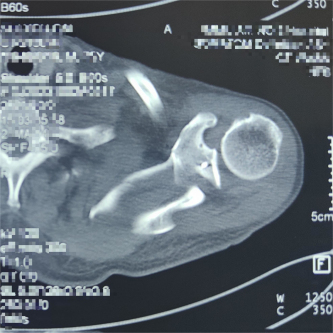

(术前X线及CT片)

患者因交通事故致伤导致左肩关节盂骨折及左肩锁关节脱位和右尺桡骨骨折,骨折移位明显,疼痛剧烈,具备手术指征。但患者为75岁高龄,基础疾病多,担心患者无法耐受过大的手术创伤。经术前讨论,创伤外科中心张立峰教授团队决定为患者应用骨科手术机器人辅助经皮内固定治疗肩关节盂骨折的手术方案。术中,通过机器人进行采集数据、并规划手术等人工智能操作,仅用1cm切口即成功完成手术。